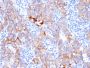

Recognizes a protein of 185 kDa, which is identified as c-erbB-2/HER-2/neu. Its epitope is localized in the extracellular domain. C-erbB-2/HER-2 is a member of the EGFR family. This MAb is specific and shows minimal cross-reaction with other members of the EGFR-family. Receptors of this family are located on the plasma membrane and consist of an extracellular ligand-binding domain that is connected to a large intracellular domain by a single transmembrane sequence. c-erbB-2/HER-2 protein is over-expressed in a variety of carcinomas especially those of breast and ovary. Primary antibodies are available purified, or with a selection of fluorescent CF® Dyes and other labels. CF® Dyes offer exceptional brightness and photostability. Note: Conjugates of blue fluorescent dyes like CF®405S and CF®405M are not recommended for detecting low abundance targets, because blue dyes have lower fluorescence and can give higher non-specific background than other dye colors.

Positive Control

SKBR-3 cells. Breast cancer tissues.

Tumor expression

Breast cancer|Ovarian cancer

IHC (FFPE) (verified)